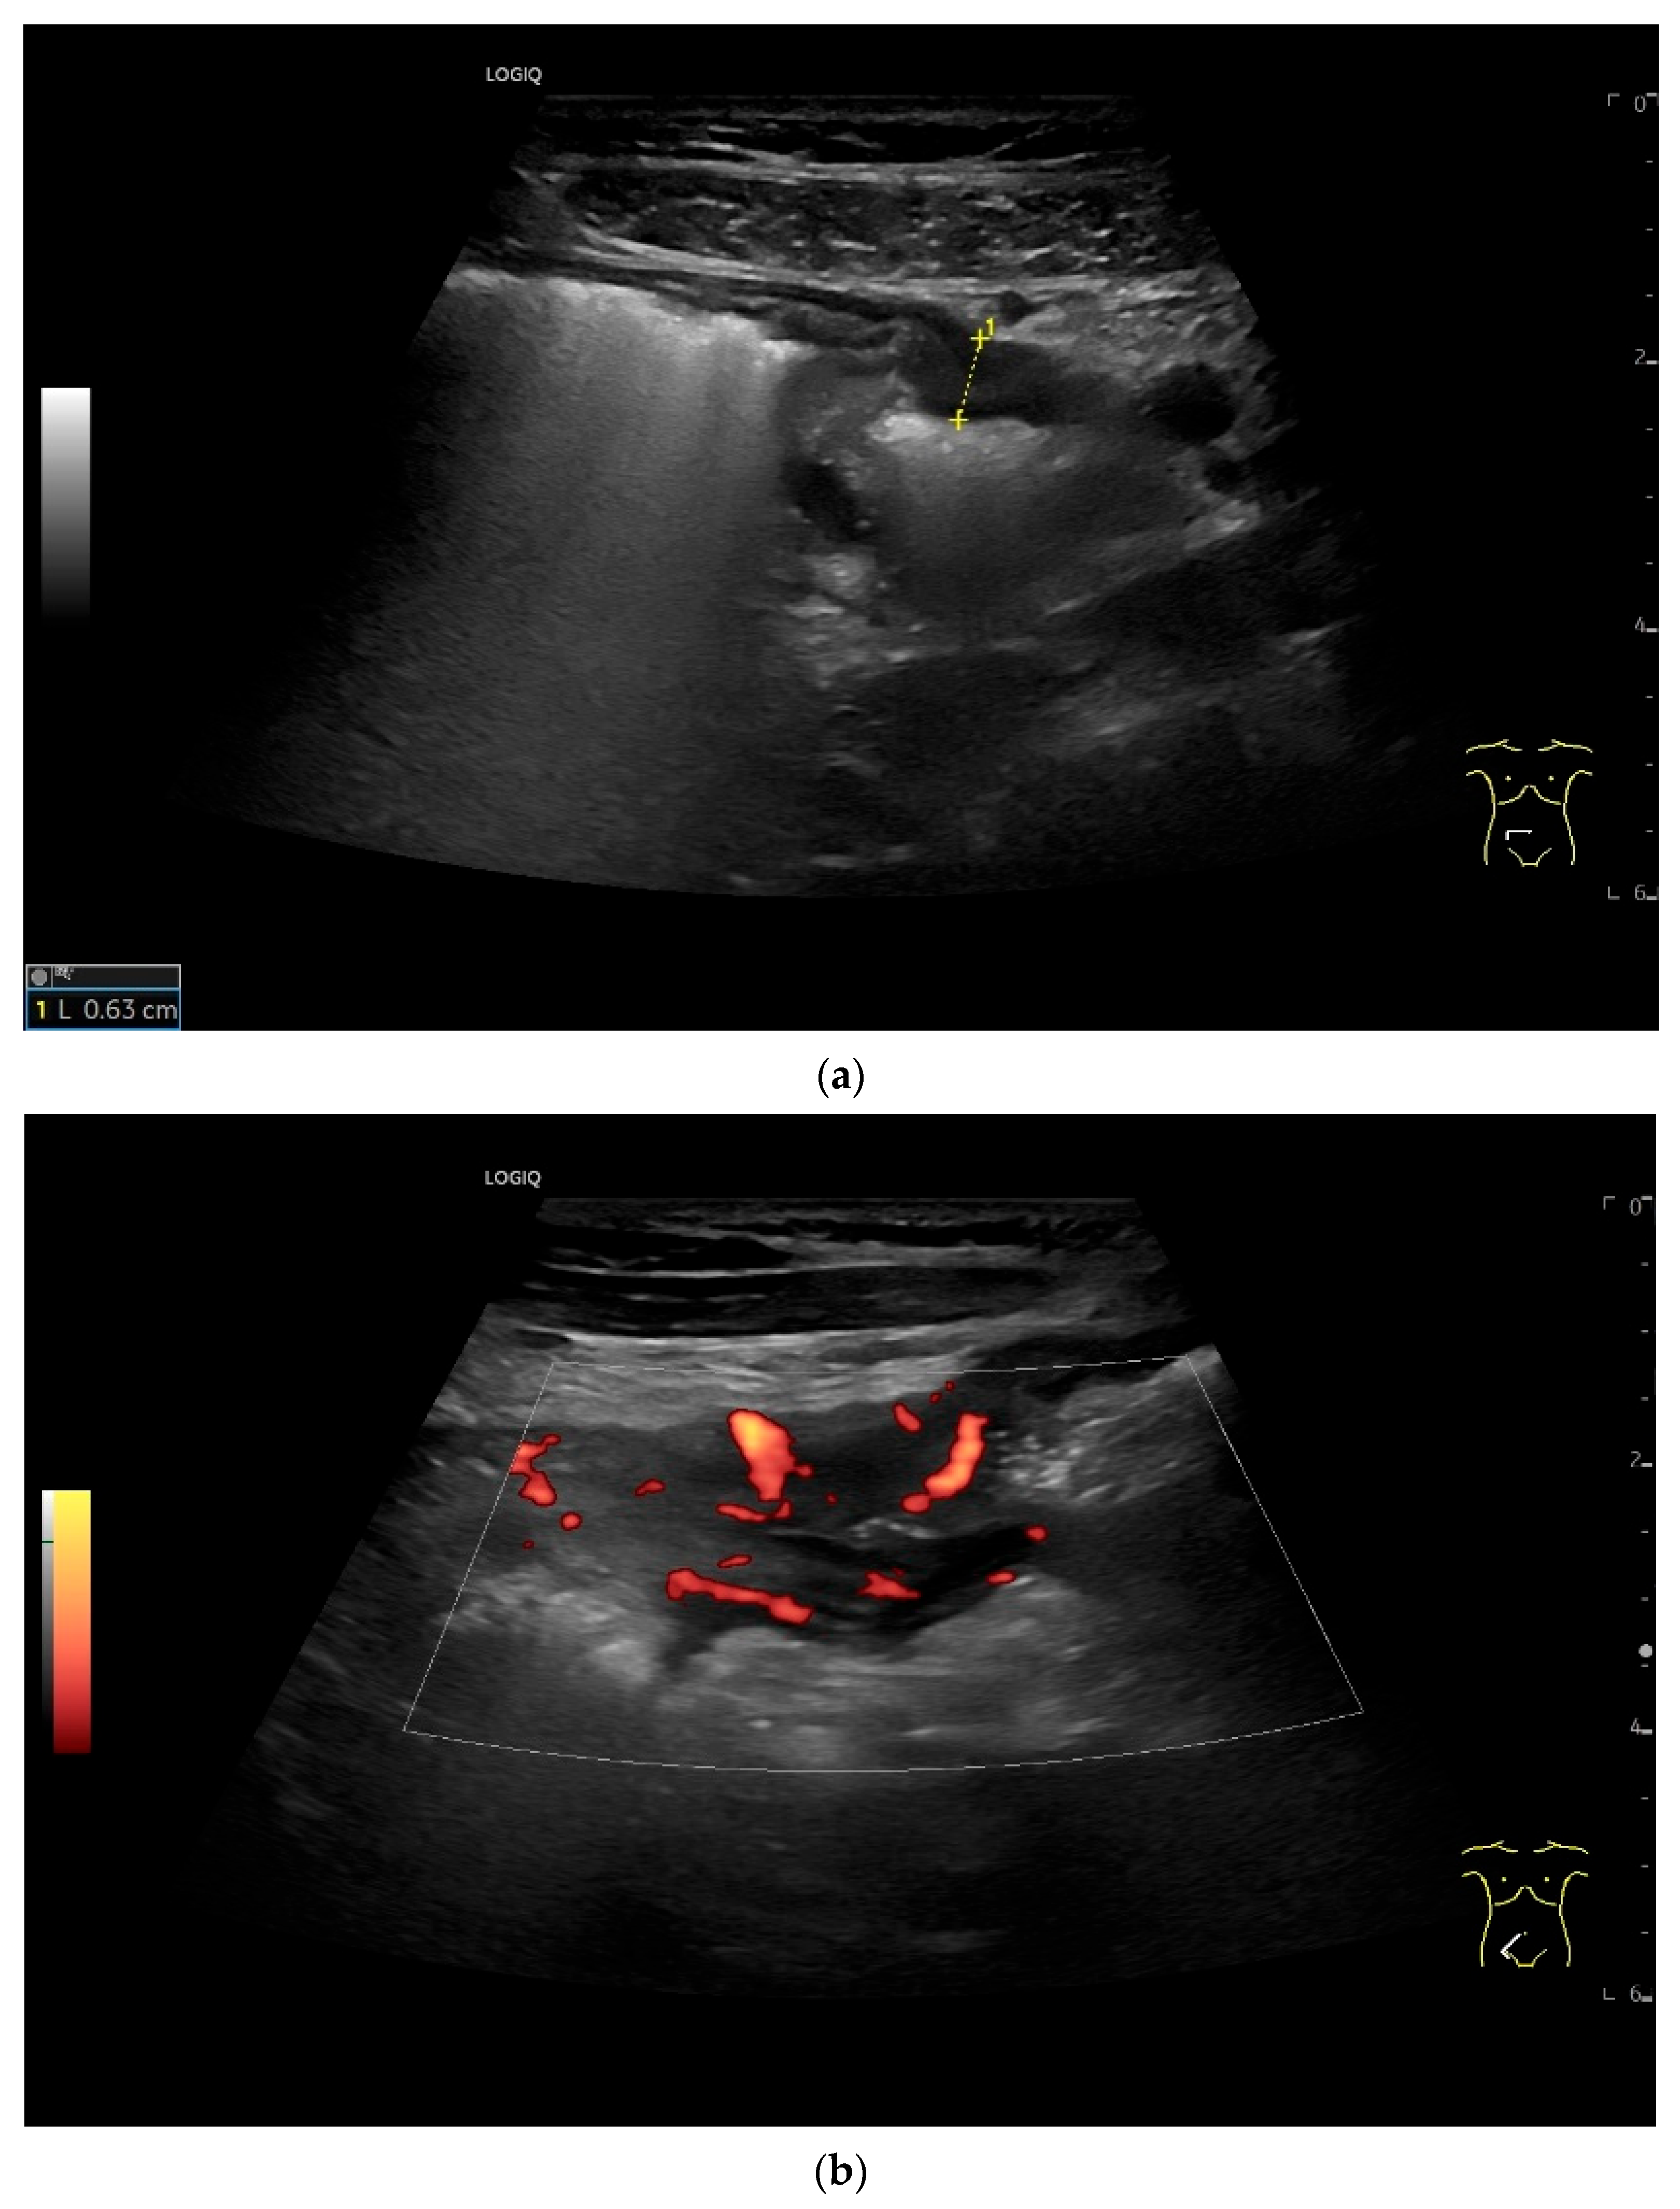

| Neuroendocrine tumor | Small, nodular hypoechoic wall thickenings, mostly in the submucosa with spreading into the other layers. Usually with small vessels on CDI. Regionally enlarged lymph nodes. Multilocular manifestations are possible. |